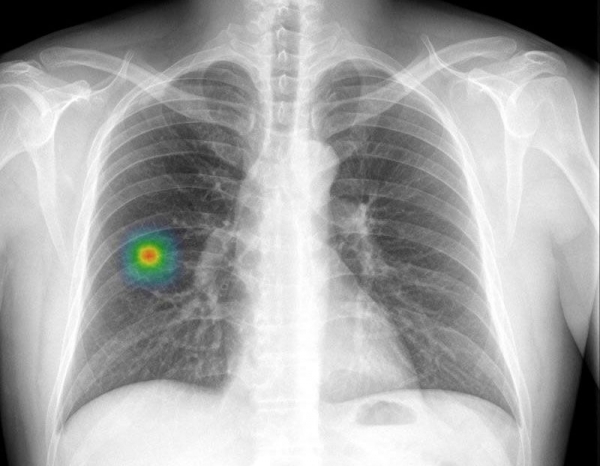

루닛에서 개발한 AI 판독 시스템 '인사이트 CXR' 흉부 판독영상

건양대병원은 9일 영상의학과 조영준 교수 연구팀이 ㈜루닛에서 개발한 주요 폐 비정상 소견 보조 소프트웨어 ‘인사이트 CXR’을 이용, 뇌출혈로 내원한 50대 남성 환자의 흉부 엑스레이 영상에서 암(편평상피암)을 찾아냈다고 밝혔다.

AI 판독 시스템은 해당 환자 폐 오른쪽 하부에서 이상징후를 포착했고 CT 등 추가 정밀검사 결과 폐암으로 확진됐다는 것이 연구팀의 설명이다.

조 교수 연구팀은 AI가 환자 응급실 내원 직후 기도삽관 뒤 촬영한 영상에선 58%의 가능성으로 이상이 있고, 며칠 후 추가 촬영한 영상에선 97%의 가능성을 제시했다고 밝혔다.